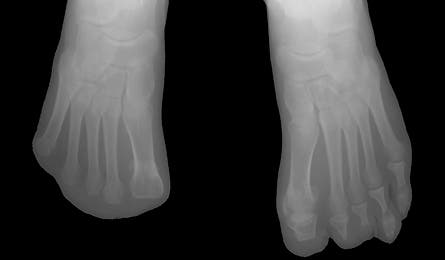

X-ray of McQueen’s Feet

The next morning, the storm cleared, allowing them to escape alive. Thawing frostbite “is the worst pain you can imagine,” reports McQueen, whose feet soon blistered and turned black. “It’s as if sharp shards of glass have ripped your flesh apart.” The extensive tissue damage cost her eight toes—and threatened to rob her of her identity as an outdoor adventurer. But less than six months later, McQueen attempted Mt. Bierstadt, another Colorado Fourteener.